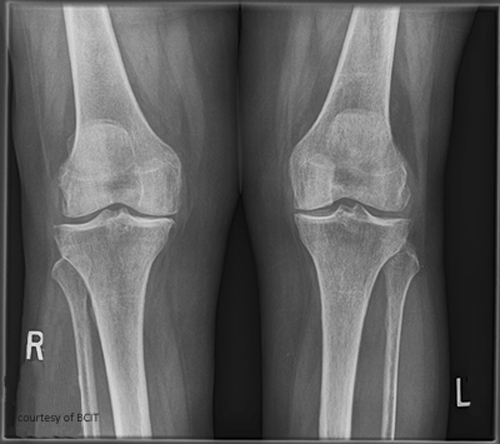

Radiographic signs of OA?

Narrowed joint space, osteophytes.

Radiographic signs of RA?

Early: minimal bony change; later: osteoporosis/rarefaction, deformities.